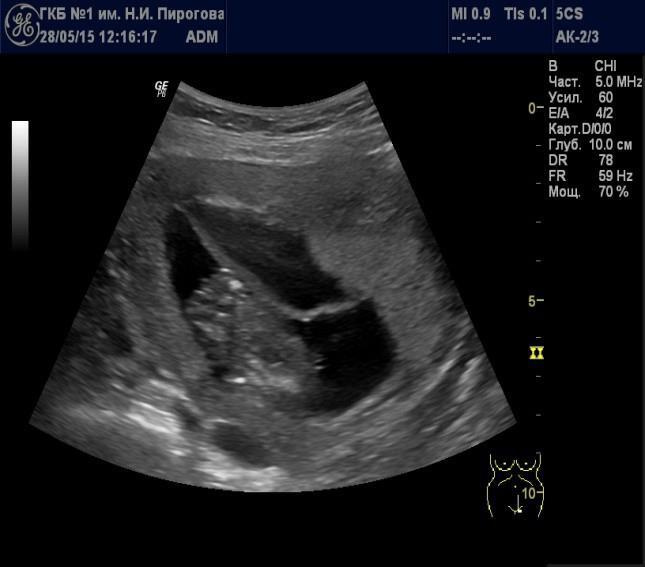

Выявляемые при серошкальном исследовании плаценты ан- или гипоэхогенные зоны чаще всего являются эхографическими срезами участков расширения ее МВП (Рис. 7) и значительно реже сосудов плода (Рис. 8). Расширение МВП может быть связано как с поступлением материнской артериальной крови, и отражать одно из состояний артериального капиллярного русла маточно-плацентарного кровотока (Рис. 9), так и с оттоком в материнское русло венозной крови (Рис. 10). При этом направление тока крови может быть установлено при цветовом допплеровском картировании (ЦДК). Следует иметь в виду, что венозное звено маточно-плацентарного кровообращения состоит из двух функциональных частей: венозных коллекторов плацентарного ложа возле разделительных септ и краевых синусов [10], которые также могут быть расширены (Рис. 11).

Участки расширения МВП могут быть различной формы (округлой, овальной, неправильной) и размеров (диаметром от нескольких миллиметров до нескольких сантиметров (Рис. 12). Их субхориальное расположение может приводить к выбуханию хориальной пластинки в амниотическую полость, характер которого может незначительно меняться в процессе проводимого исследования.

Расширение участков МВП при плацентографическом исследовании во второй половине беременности (после 20 нед.) регистрируется с частотой от 2 до 18%. Их выявление в количестве не менее 3-х и размерами не менее 20 мм трактуется как регистрация «плацентарных озер» [34]. Уместно подчеркнуть, что выраженное расширение МВП плаценты приводит к ее увеличению, о чем можно судить по ее толщине.

Рис. 12. Беременность 34 нед. Расширение межворсинкового пространства, связанное с венозным оттоком в режиме цветового допплеровского картирования (направление низкоскоростного движения крови было установлено визуально в режиме реального времени).